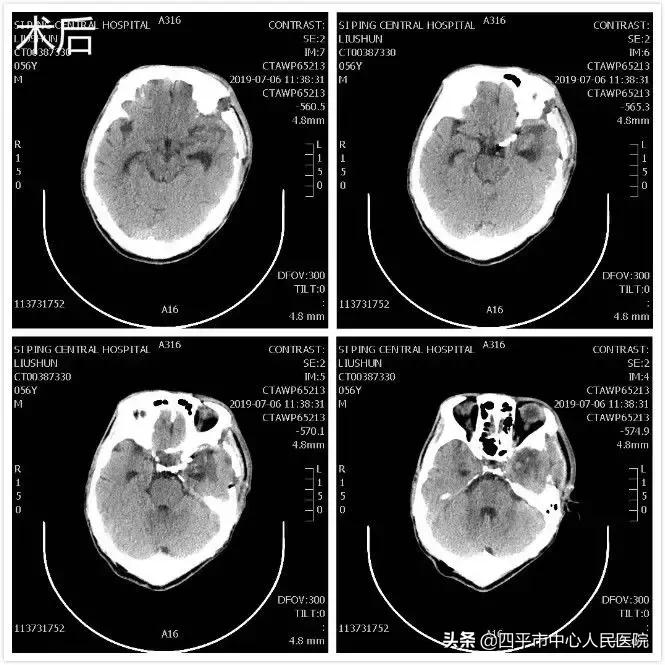

Case4 大量蛛网膜下腔出血颅内动脉瘤开颅探查术

患者张XX,于入院前2小时突发神志不清,伴恶心呕吐,呕吐物为胃内容物,四肢不动,伴尿*禁失**,无抽搐。由家属送至梨树县医院,行头CT检查提示脑出血,为求进一步治疗转送至我院,我院神经内科给予复查头CT提示大量蛛网膜下腔出血,首先颅内动脉瘤破裂所致,由于患者到我院时深度昏迷状态,呼吸微弱,HUNT-HESS分级5级,不适合行头部CTA检查及介入栓塞治疗,家属强烈要求手术治疗,请麻醉科行气管插管后入手术室,李晓东主任带领马龙急诊全麻下经左侧扩大翼点入路行右侧脑室外引流术及颅内动脉瘤探查术,术中探查患者左侧后交通动脉巨大瘤,临时阻断颈内动脉后给予确切夹闭,术中动脉瘤没再次有破裂出血。术后第1天,患者呈浅昏迷状态,刺痛可定位,四肢可自主活动。复查头部CT满意,查头部CTA见左侧后交通动脉瘤夹闭确切。但患者于术后第3天,出现迟发性脑内血肿,考虑到预后不好,家属放弃治疗出院,临出院时对我科李晓东主任及马龙医生的积极救治表示感谢。